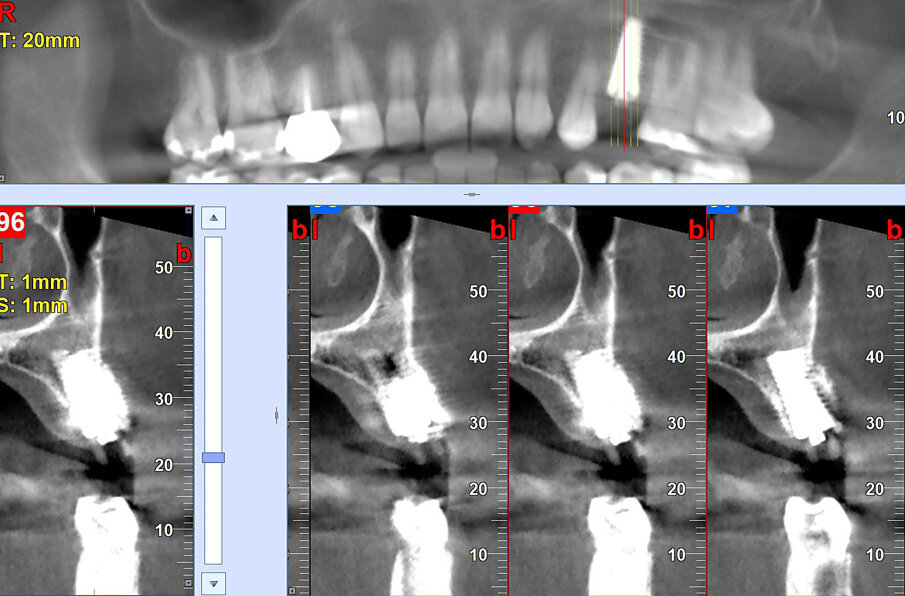

La paziente presentava un primo premolare superiore sinistro non recuperabile. La CBCT mostra la situazione iniziale (Fig. 1). Si noti quella che appare come una grande fenestrazione buccale nell’area della resezione radicolare (Fig. 2). Il dente fratturato è stato estratto (Figg. 3, 4). Lo scollamento del lembo di accesso rivela la fenestrazione buccale (Fig. 5). L’osteotomia è stata preparata secondo il protocollo di fresatura di Neoss ProActive Edge (Fig. 6). Successivamente viene posizionato un impianto Neoss ProActive Edge Ø 5.0 × 13 mm (Fig. 7). L’impianto è stato posizionato in una situazione di disponibilità ossea molto limitata e densità ossea media (Fig. 8). Nonostante le limitazioni dovute alla condizione ossea, è stata raggiunta una buona stabilità primaria. È stato utilizzato un torque di inserimento di 20 Ncm, l’ISQ è risultato in un range di 70/77. Per correggere la fenestrazione buccale è stato eseguito un innesto con particolato osseo di origine porcina (Fig. 9). L’innesto osseo è stato coperto con una membrana di collagene riassorbibile (Fig. 10). Il lembo mucoso è stato suturato attorno al pilastro di guarigione in PEEK, consentendo la guarigione in una sola fase (Fig. 11).

La radiografia mostra il posizionamento dell’impianto (Fig. 12). Sul pilastro di guarigione è stato montato uno ScanPeg (Fig. 13), ed è stata presa un impronta digitale del sito con uno scanner intraorale (Fig. 14). La CBCT effettuata a 3,5 mesi di guarigione (Fig. 15) mostra una buona integrazione dell'impianto Edge e della rigenerazione ossea nel difetto iniziale. L'ISQ è aumentato fino a 72/79, indicando un'ulteriore buona integrazione. Utilizzando un flusso di lavoro completamente digitale, è stato fabbricato un pilastro in zirconia personalizzato su un Neoss TiBase (Fig. 16) ed è stata montata una corona in zirconia sul pilastro (Fig. 17).